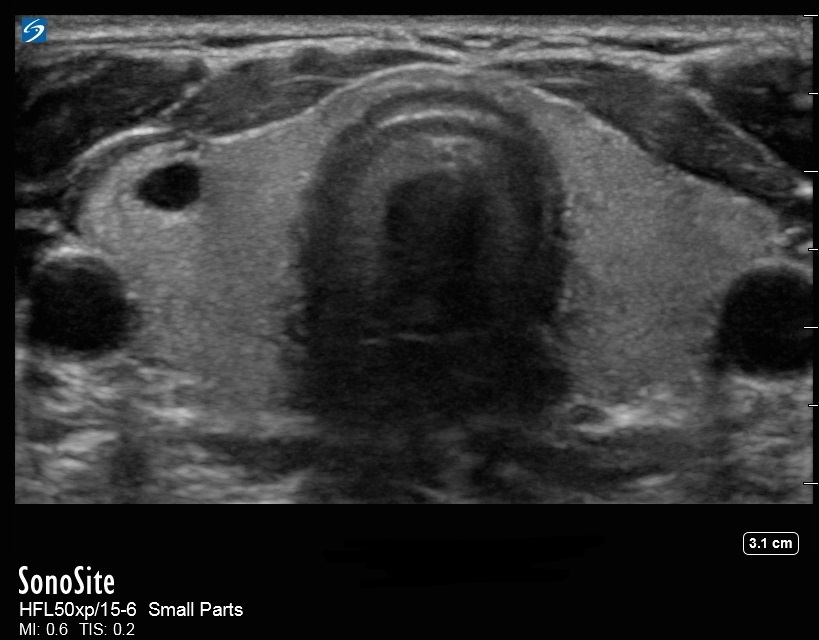

甲状腺囊肿图像